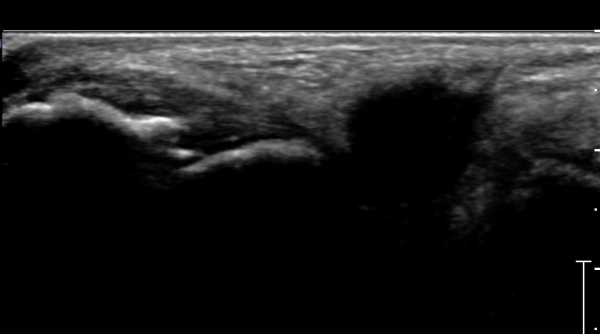

Àü°ÅºñÀδë Á¾´Ü¸é°Ë»ç»ó Àü°ÅºñÀδëÀÇ Àú¿¡ÄÚ À§Ãà°ú Á·±Ùµ¿(sinus tarsi) ¼ö¾×Àú·ù°¡

°üÂûµÈ´Ù(»çÁø 2, 3).